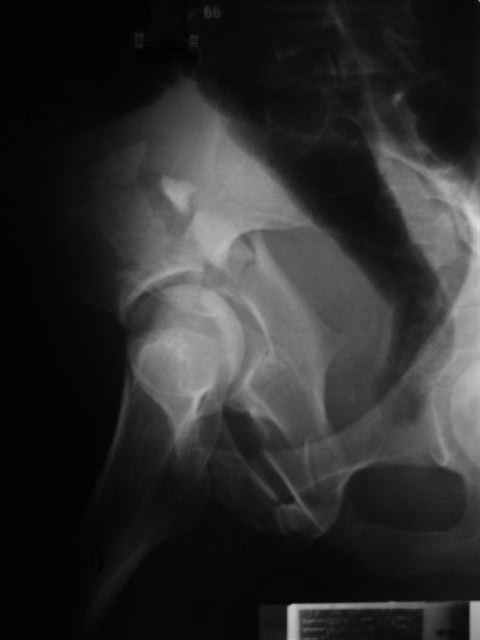

Уважаемые коллеги, 43 летний мужчина, попав в автоаварию 13.10.2004, получил оскольчатый перелом обеих колонн левой вертлужной впадины.

общее состояние стабильное, повреждений внутр. органов и нейро-сосудистых нарушений не отмечено. Заранее признателен за советы и комментарии экспертов. Евгений И. Чекашкин